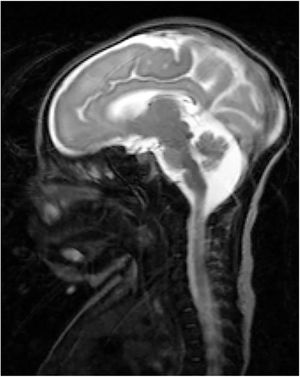

Our patient was a full-term neonate with intrauterine growth retardation from week 34. The pregnancy was uneventful. The parents were nonconsanguineous and the baby was born by normal vaginal delivery. Birth weight was 2470 g (P2; –2.18 SD), length was 43 cm (P2; –2.3 SD), and head circumference was 30 cm (< P1; –3.21 SD). Two hours after birth, the child started to make sucking motions, which were subsequently associated with clonic movements of the face and left arm, lasting 4 min. The patient presented similar episodes during the first 24 h of life, which resolved with phenobarbital. We performed an aetiological study of neonatal seizures. A blood count revealed thrombocytosis and slightly elevated thyroid hormone levels. An electroencephalography study detected no alterations. Transfontanellar ultrasound revealed thinning of the corpus callosum and mega cisterna magna. In addition to these findings, a brain MRI scan (Fig. 1) also revealed partial atrophy of the cerebellar vermis and moderate sulcal underdevelopment in the frontal and occipital regions, compatible with LCH. The patient received treatment with phenobarbital, levetiracetam, and clobazam due to poor seizure control. A month and a half after birth, a follow-up blood test revealed cholestasis (total bilirubin 6.8 mg/dL, conjugated bilirubin 5.3 mg/dL, gamma-glutamyl transferase 2120 IU/L). An analysis of alpha-1 antitrypsin levels, a study of hormonal and metabolic function and infections, and an abdominal ultrasound revealed no abnormalities. We suspected EBA and decided to administer conservative treatment due to the patient’s poor prognosis. A genetic study of lissencephaly and congenital disorders of glycosylation yielded negative results. At 7 months of life, the patient was brought to hospital due to fever and decompensation of the underlying liver disease; despite medical treatment, she died due to cardiorespiratory arrest. A post-mortem liver biopsy confirmed the diagnosis of EBA. This is the first case of LCH associated with EBA to be reported in the literature. To date, no study has described mutations linking LCH and EBA.